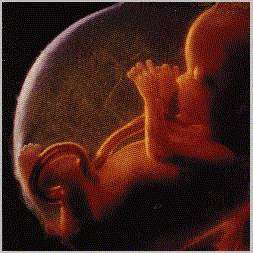

34 haftalık bebek Doğuma çok az kaldı.

Bebeğiniz doğum pozisyonu almak için iyice aşağıya doğru iyice yerleşiyor. Minik bebeğinizin bağışıklık sistemi de gittikçe güçleniyor. Artan kilolardan dolayı ağırlığınız arttı ve uyumakta zorlanıyorsunuz ama dayanın çok az kaldı.